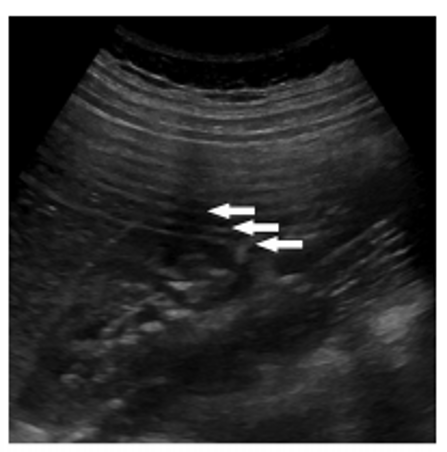

The artifact shown is reverberation caused by back and forth reflection of the ultrasound beam between 2 closely spaced interfaces. These reverberation echoes appear as multiple equally spaced lines, which decrease in intensity with increasing depth. This artifact is often caused by highly reflective interfaces, e.g., metallic objects or calcification in tissues.

reverberation artifact:

multiple equidistance echoes